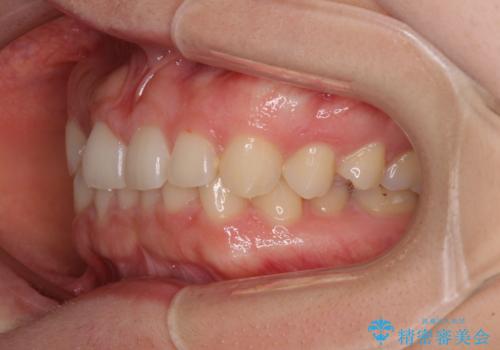

- 前歯の隙間やクロスバイトを気にして来院された患者様です。

ギリギリとなりましたが、結婚式直前にワイヤー装置を外すことができました。

ワイヤー装置除去後に細かい部分を短期間のマウスピース矯正にて仕上げました。